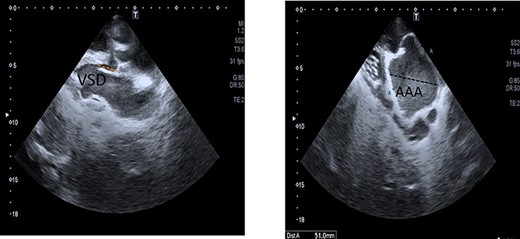

(A) Chest X-ray showed prominent pulmonary vascular marking, atelectasis in the right lung and cardiomegaly with a widening mediastinum. (B and C) Echocardiography: short-axis view revealed VSD (B) and long-axis view showed ascending aortic aneurysm (C).

Echocardiography was done and a short-axis view revealed that the right and left pulmonary artery originate from common arterial trunk with no main pulmonary artery segment. The long-axis view showed a VSD and an ascending aortic aneurysm (Fig. 1B and C). Contrast chest computer tomography (CT) showed the ascending aorta and main pulmonary arteries originate from a single common trunk (Fig. 2A and B).